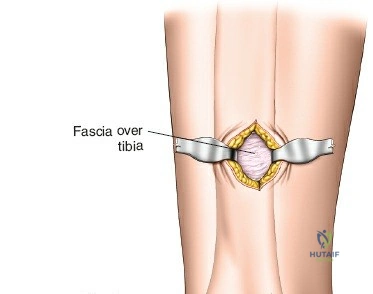

Incision Planning and Soft Tissue Dissection

- Incision Selection:

- Anteromedial Approach: Often preferred. A longitudinal incision, typically 3-5 cm, is made proximally and another similar incision distally (or a single longer incision) along the anteromedial aspect of the tibia. The proximal incision is placed away from the fracture zone and the distal incision is typically just proximal to the joint line, usually aligning with the non-articular part of the medial malleolus. The superficial peroneal nerve and saphenous nerve and vein must be identified and protected.

- Direct Anterior Approach: Can also be utilized, with incisions typically placed over the interval between the tibialis anterior and extensor hallucis longus muscles. The deep peroneal nerve and anterior tibial vessels lie deeper and must be protected.

- Subcutaneous Tunnel Creation: After skin incisions, subcutaneous dissection is performed to elevate skin flaps minimally. A submuscular or subcutaneous tunnel is then created, connecting the proximal and distal incisions. This tunnel should be just wide enough to accommodate the plate. Blunt dissection (e.g., using a blunt elevator, specialized plate insertion guide, or fingers) is critical to preserve the periosteum overlying the fracture fragments, which maintains their blood supply and vitality.

- Protection of Neurovascular Structures: Meticulous care must be taken to identify and protect superficial peroneal nerve branches (anterolateral aspect), saphenous nerve and vein (anteromedial aspect), and deep peroneal nerve and anterior tibial vessels (anterior compartment).